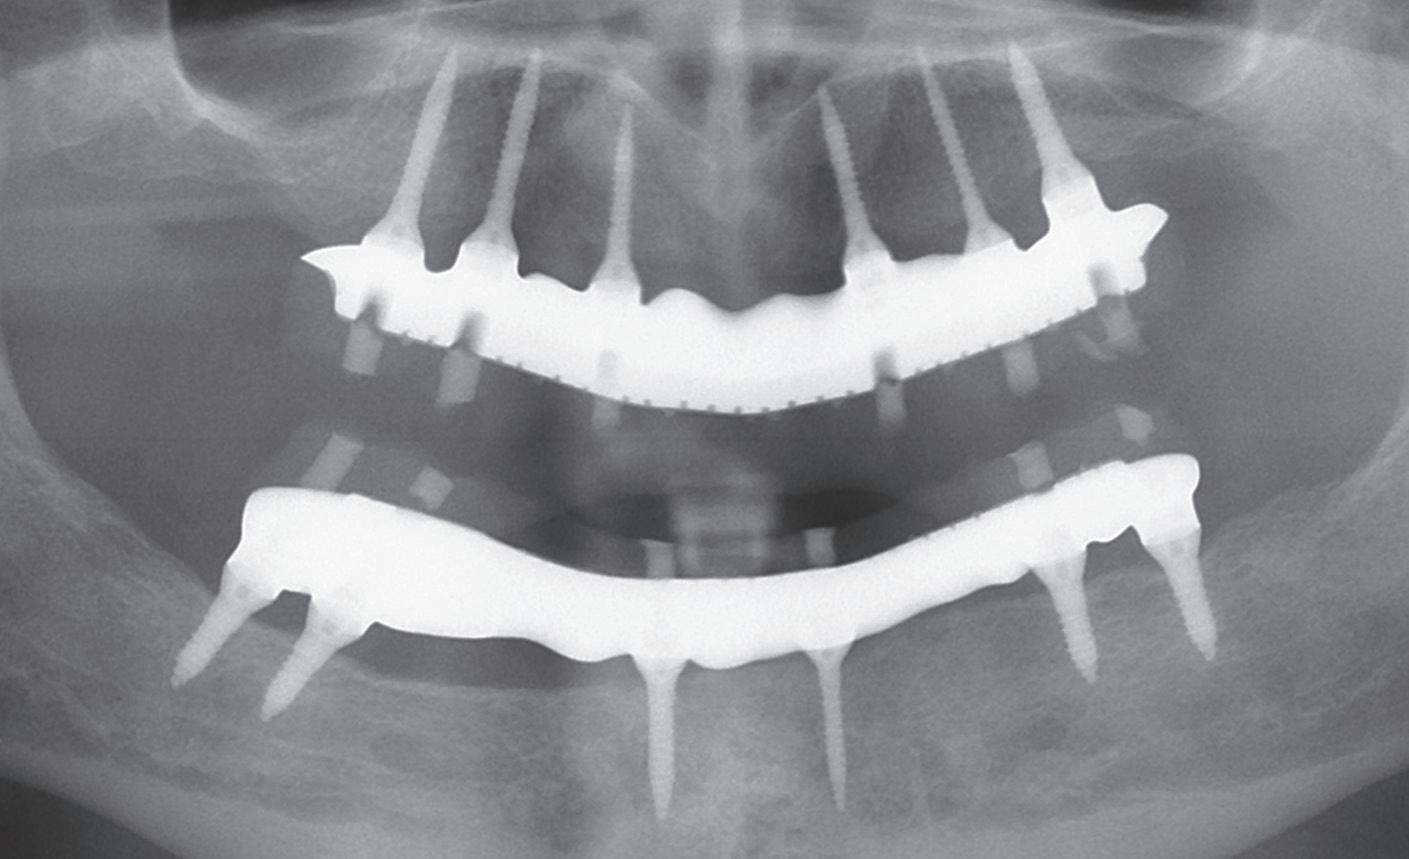

Miniature Implants: A unique system for minimally invasive treatment

This is an exclusive training course on the BioMiniatures Miniature Implant system, offering an opportunity to be the first to learn about this innovative system. The course includes hands-on education on the use of Miniature Implants for full and partial arch rehabilitation using a minimally invasive approach. Miniature Implants are narrow diameter implants with a unique self-drilling and self-advancing design which allows placing implants in very narrow alveolar ridges without needing complex and risky bone augmentation procedures. The course will enable you to restore dentitions in severely atrophic ridges with simplicity and confidence. This will include both surgical and prosthetic procedures.